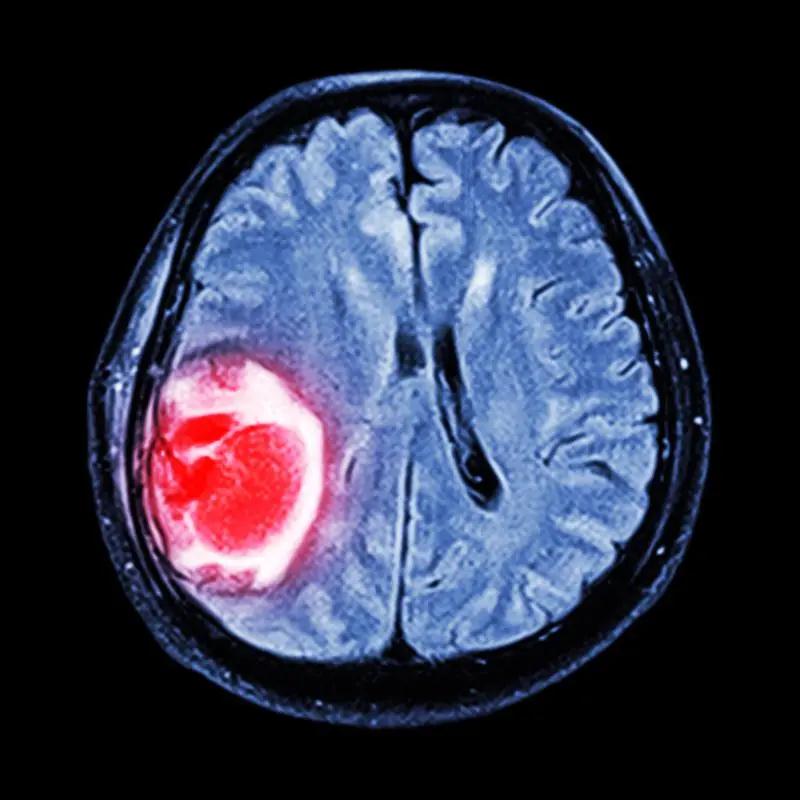

哪些腫瘤適合質子重離子治療?

質子重離子可治療癌種多,包括淋巴瘤(有影像可見病灶)、腦腫瘤(顱底)、頭頸部腫瘤(肉瘤)、縱隔腫瘤(早期食管癌)、肺癌(非小細胞)、腎盂癌/輸尿管癌/膀胱癌、肝癌(單發(fā)/位于相鄰區(qū)域)、胰腺癌、直腸癌盆腔復發(fā)、前列腺癌在內的腫瘤,均可進行質子重離子治療。

質子重離子治療與外科手術結合效果更佳

質子重離子治療可作為多種惡性腫瘤(如鼻咽癌、前列腺癌等)的主要根治性治療手段,治療的效果與手術相當,且能更大限度保留器官功能,提高患者的生存質量。

與此同時,質子重離子治療與手術的配合成為臨床應用中的一大亮點。如肺癌、腦膠質瘤、腺樣囊性癌等惡性腫瘤手術后進行輔助放療,利用質子重離子“精準爆破”的優(yōu)勢,可以消滅殘存的腫瘤細胞,從而提高腫瘤控制率及患者生存率。再如晚期食管癌、直腸癌等惡性腫瘤,原本難以進行手術切除,通過質子重離子新輔助放療(術前放療)后腫瘤體積縮小,增加了手術切除的成功幾率,且有利于降低術中腫瘤播散的可能性。